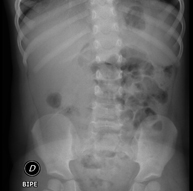

- Abdomen X-ray

This technique uses X-ray rendered imaging for examining the abdomen (stomach, small intestine, large intestine, liver, kidneys, bladder, bony pelvis, etc.).

An abdominal X-ray uses a small dose of radiation to obtain a two-dimensional image of the abdomen with its anatomical structures (stomach, small intestine, large intestine, liver, pancreas, kidneys, bladder, bony pelvis, etc.).